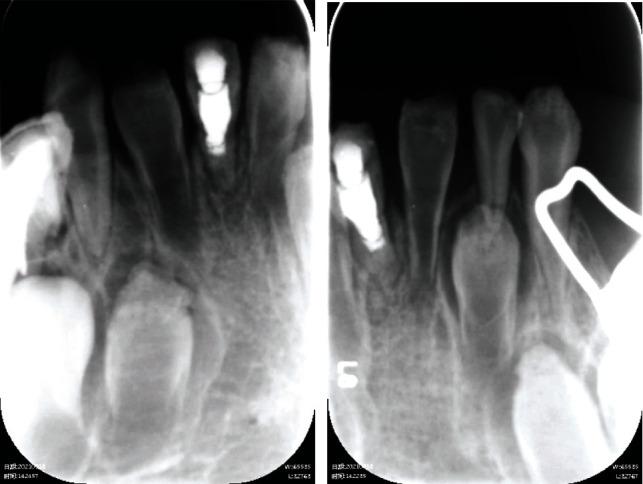

Pulp involvement of immature permanent teeth with dentinogenesis imperfecta is challenging and could lead to extraction. A case of dentinogenesis imperfecta-induced periapical periodontitis of an immature permanent tooth was treated with regenerative endodontic treatment (RET), and root maturation was observed in 12-month follow-up. An 8-year-old girl presented acute pain and swelling in central mandibular region. Clinical and radiographic examination revealed "shell teeth" appearance of teeth 31, 41, and 42. Periapical lesion of tooth 31 was observed. Tooth 41 was previously treated with apexification. RET was planned and carried out for the necrotic tooth (tooth 31) with dentinogenesis imperfecta. The 1-, 3-, 7-, and 12-month postoperative recall revealed complete healing of periapical lesions. Root maturation characterized by elongation of root, thickening of dentinal walls, and closure of root apex was observed with radiographic examinations. We show that RET could be a desirable treatment for necrotic immature permanent teeth with dentinogenesis imperfecta and lead to resolution of endodontic lesions as well as maturation of dental root. The findings of this case suggest that RET should be considered by endodontist and pediatric dentist to treat teeth with similar dental anomalies and apical periodontitis.

患有牙本质发育不全的年轻恒牙牙髓受累情况具有挑战性,可能导致牙齿拔除。一例牙本质发育不全引起的年轻恒牙根尖周炎采用牙髓再生治疗(RET)进行治疗,并在12个月的随访中观察到牙根成熟。一名8岁女孩下颌中部区域出现急性疼痛和肿胀。临床和影像学检查显示31、41和42号牙呈“壳牙”外观。观察到31号牙有根尖病变。41号牙先前已进行根尖诱导成形术。计划并对患有牙本质发育不全的坏死牙(31号牙)实施RET。术后1、3、7和12个月的复查显示根尖病变完全愈合。影像学检查观察到牙根成熟,其特征为牙根伸长、牙本质壁增厚和根尖闭合。我们表明,RET可能是治疗患有牙本质发育不全的坏死年轻恒牙的理想方法,并可导致牙髓病变的消退以及牙根的成熟。该病例的结果表明,牙髓病医生和儿童牙医应考虑采用RET来治疗具有类似牙齿异常和根尖周炎的牙齿。